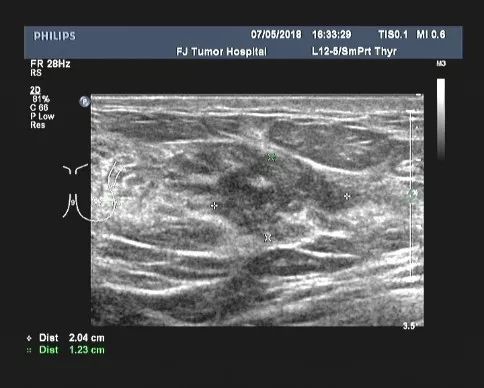

2018-05-25、2018-06-14改为nab-PHL方案(白蛋白结合型紫杉醇400mg+曲妥珠单抗408mg+拉帕替尼1000mg )化疗2周期。

▎疗效评估:B超(2018-07):左乳2-3点处探及一低回声区,大小约2.2cm×1.4cm,边缘不规则,可见成角、毛刺,内部回声不均;左腋中、下组探及数个低回声,大者约1.6cm×0.7cm(腋中组)、0.9cm×0.5cm(腋下组),边界尚清,类圆形,皮髓质分界不清,皮质不规则增厚,淋巴结门消失,右乳及右腋窝未见异常。